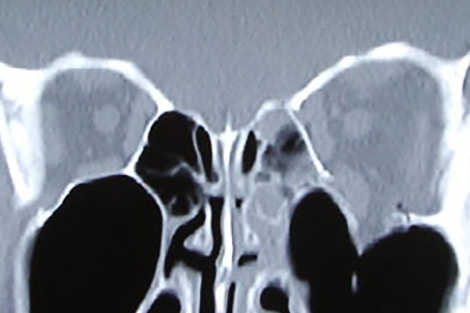

●眼窩壁骨折

眼窩疾患については、その診断と治療の適応の評価が、研修期間の重点目標です。代表疾患には、眼窩壁骨折、眼瞼下垂や眼瞼内反などの眼瞼形成、涙道疾患などが挙げられます。